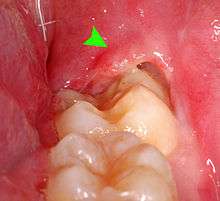

When wisdom teeth communicate with the mouth, the most common symptom is localized pain, swelling and bleeding of the tissue overlying the tooth. This tissue is called the operculum and the disorder called pericoronitis which means inflammation around the crown of the tooth.[3]:141 Low grade chronic periodontitis commonly occurs on either the wisdom tooth or the second molar, causing less obvious symptoms such as bad breath and bleeding from the gums. The teeth can also remain asymptomatic (pain free), even with disease.[5] As the teeth near the mouth during normal development, people sometimes report mild pressure of other symptoms similar to teething.

Where there is an operculum of gingiva overlying the tooth that has become infected it can be treated with local cleaning, an antiseptic rinse of the area and antibiotics if severe. Definitive treatment can be excision of the tissue, however, recurrence of these infections is high. Pericoronitis, while a small area of tissue, should be viewed with caution, because it lies near the anatomic planes of the neck and can progress to life-threatening neck infections.[12]:440–441